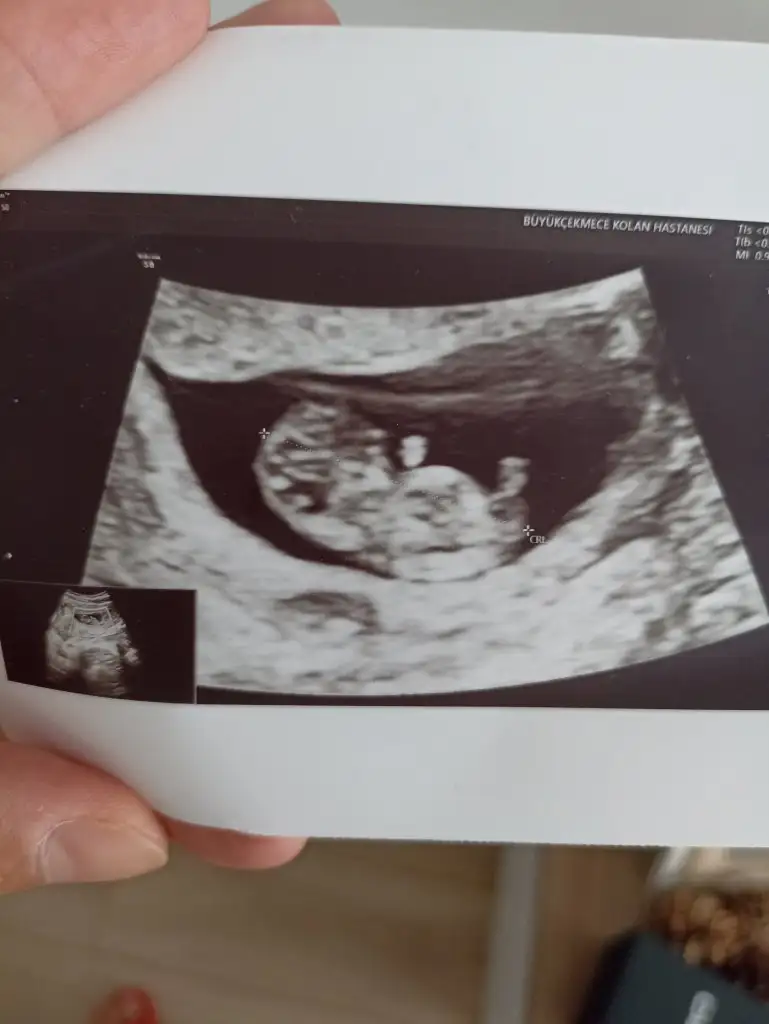

Evet canm ilkten bacaklar kapalıydı göstermedi yarım saat sonra tekrar bakti geçen haftada mınık bisey vardı yıne aynı 14+1 ı'm net brsy demedi çıkıntıda büyüme yok hayla ufak dedı yanılma da olabilir hafta tekrar bakacak çok merak ediyorum

• IMG-20230612-WA0045.webp

IMG-20230612-WA0045.webp

26,9 KB · Görüntüleme: 103

• IMG-20230612-WA0042.webp

IMG-20230612-WA0042.webp

27,2 KB · Görüntüleme: 102

Sen neye benzettin